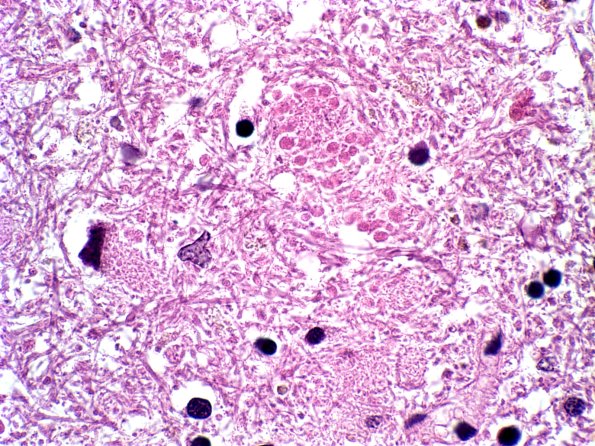

8B14 PSP (Case 8) Grumose Dentate b

Dentate neurons exhibit grumose degeneration. (H&E)